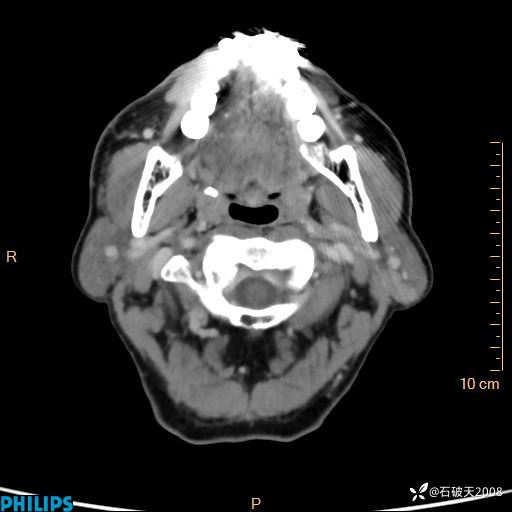

病例分享:老年男性,颈部占位,一周后公布病理

胡志勇HZY 达人已点赞男 61岁 主 诉:发现左侧面部肿物1年余。

现病史:患者于1年余前无意间发现左侧耳下有一肿物,大小如“花生米样”,无压痛,无明显红肿,无畏寒、发热,无咳嗽、咳痰,无盗汗、心慌,无手足颤动、胸闷及性格改变,未在意,未给予特殊处理,2天前至我院行彩超示: 左侧腮腺内低回声(考虑肿大淋巴结),现患者为求进一步诊治,遂来我院就诊,门诊以“局部肿物”为诊断收住我科。自发病来,患者神志清,精神可,饮食睡眠尚可,大小便正常,近期体重无下降。

平扫